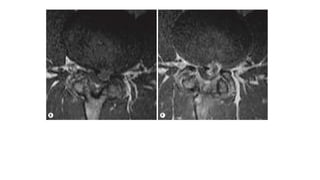

Redundant Nerve Roots. T2 weighted (A) and magnetic

resonance (MR) myelography (B) images. Postoperative status

after laminectomy at L2 to L3 for a spinal canal stenosis.

Sagittal T2 weighted image and the myelo-MR shows residual

redundant nerve roots of the cauda equina proximal to the

previous spinal canal stenosis.